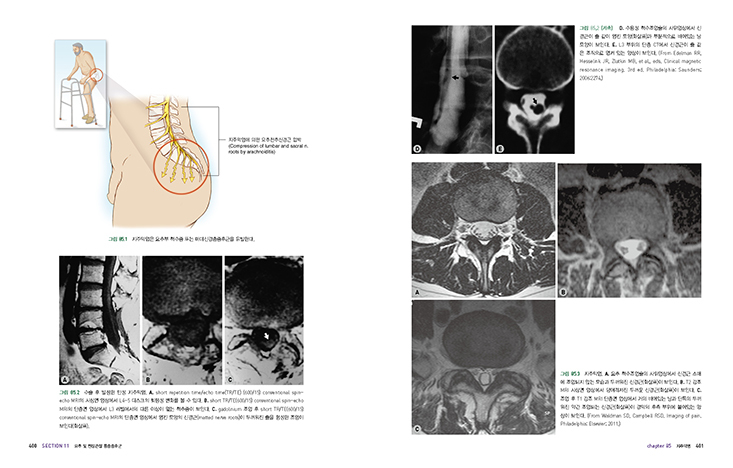

085 지주막염

086 추간판염